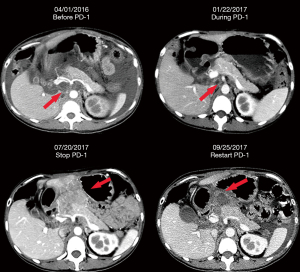

Eight months (September 17th, 2013) after the nephrectomy, a follow-up CT scan observed relapse at the RPLNs and right-side psoas muscle metastasis. Sunitinib (50 mg QD, 4 weeks on, 2 weeks off) was prescribed and she achieved partial response (PR). Twenty-eight months (January 1st, 2016) later, she gradually developed ascites, characterized by abdominal distention and shortness of breath, which were not improving despite second-line treatment with axitinib (5 mg, QD) for 3 months. Subsequently, she received pembrolizumab (20 mg Q2W with cytokine-induced killer cells) concurrent with axitinib. As a result, a significant reduction in ascites was observed and she restarted working in June 2016. However, due to economic issues, she stopped pembrolizumab in January 2017 and the RPLN progressed shortly after two weeks. She restarted pembrolizumab (20 mg Q2W) from July 2017 and achieved PR again (Figure 3). In December 2017, she stopped pembrolizumab because of disease progression identified by two enhanced mass lesions at the splenic hilum and subcutaneous abdominal wall.